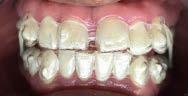

Se presenta una paciente clase ll esquelética en los estudios extrao rales en la fotografía de frente se ve hiperdivergente con una mordi da profunda de 5mm, un diastema, y refiere como motivo de consulta "no me gusta el espacio entre mis dien tes" (Figura 1).

En los estudios intraorales de inicio en las fotografías se muestra en la de frente el diastema anterior, con la línea media dental superior e inferior no coincidentes, la mordida profun da anterior (Figura 2), en la lateral derecha clase l molar y canina bila teral (Figura 3), el apiñamiento leve superior e inferior y la forma de las arcadas.

Figura 1. Extraoral de inicio de frente. Figura 2. Intraoral de frente derecha, izquierda. Figura 3. Oclusal superior e inferior arcadas cuadrada. Figura 4. Radiografía lateral de cráneo. Figura 5. Rx Panorámica.